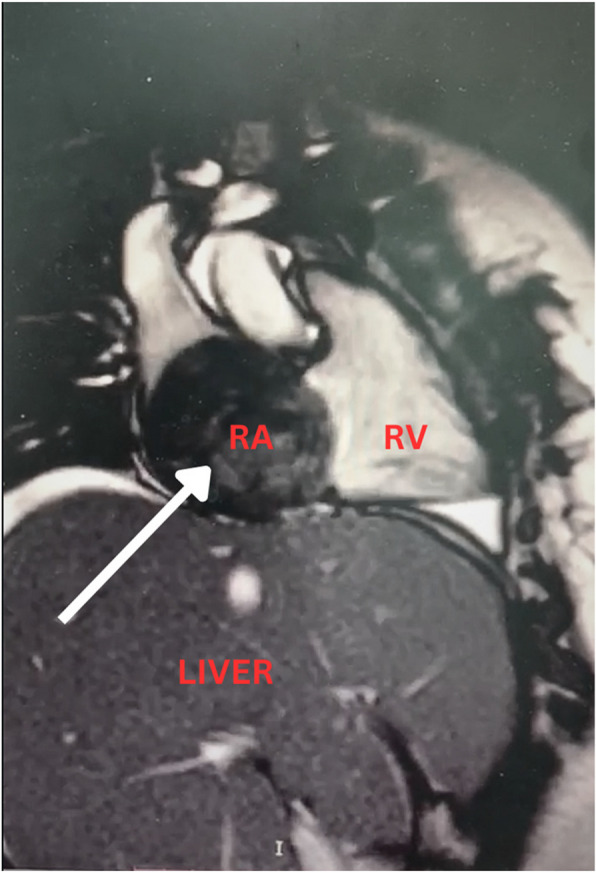

心房黏液瘤是最常见的原发性心脏肿瘤。20%的病例起源于右心房。据报道,只有少数此类肿瘤起源于下腔静脉。我们报告一例20岁女性复发性呕吐和室上心动过速(SVT),发现有一个巨大的黏液瘤出现在肝上下腔静脉(IVC),累及咽鼓管瓣膜,并延伸到右心房。手术切除是成功的,导致平静的恢复。本病例强调了及时诊断和手术干预治疗右心房黏液瘤的重要性,以防止潜在的并发症,如栓塞和猝死。

Atrial myxomas are the most common primary cardiac tumors. In 20% of cases, they arise from the right atrium. Only a few such tumors are reported to have arisen from the inferior vena cava. We present the case of a 20-year-old female with recurrent vomiting and supraventricular tachycardia (SVT), found to have a massive myxoma emerging from the suprahepatic Inferior vena cava (IVC) involving the eustachian valve, and extending to the right atrium. Surgical excision was successful, leading to an uneventful recovery. This case underscores the importance of prompt diagnosis and surgical intervention in managing right atrial myxomas to prevent potential complications such as embolism and sudden death.